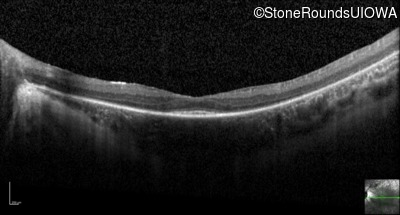

Optical Coherence Tomography - Right - 20/100 -2

Exemplar / OCT Stack

OCT Stack

Optical Coherence Tomography - Left - 20/100 -2